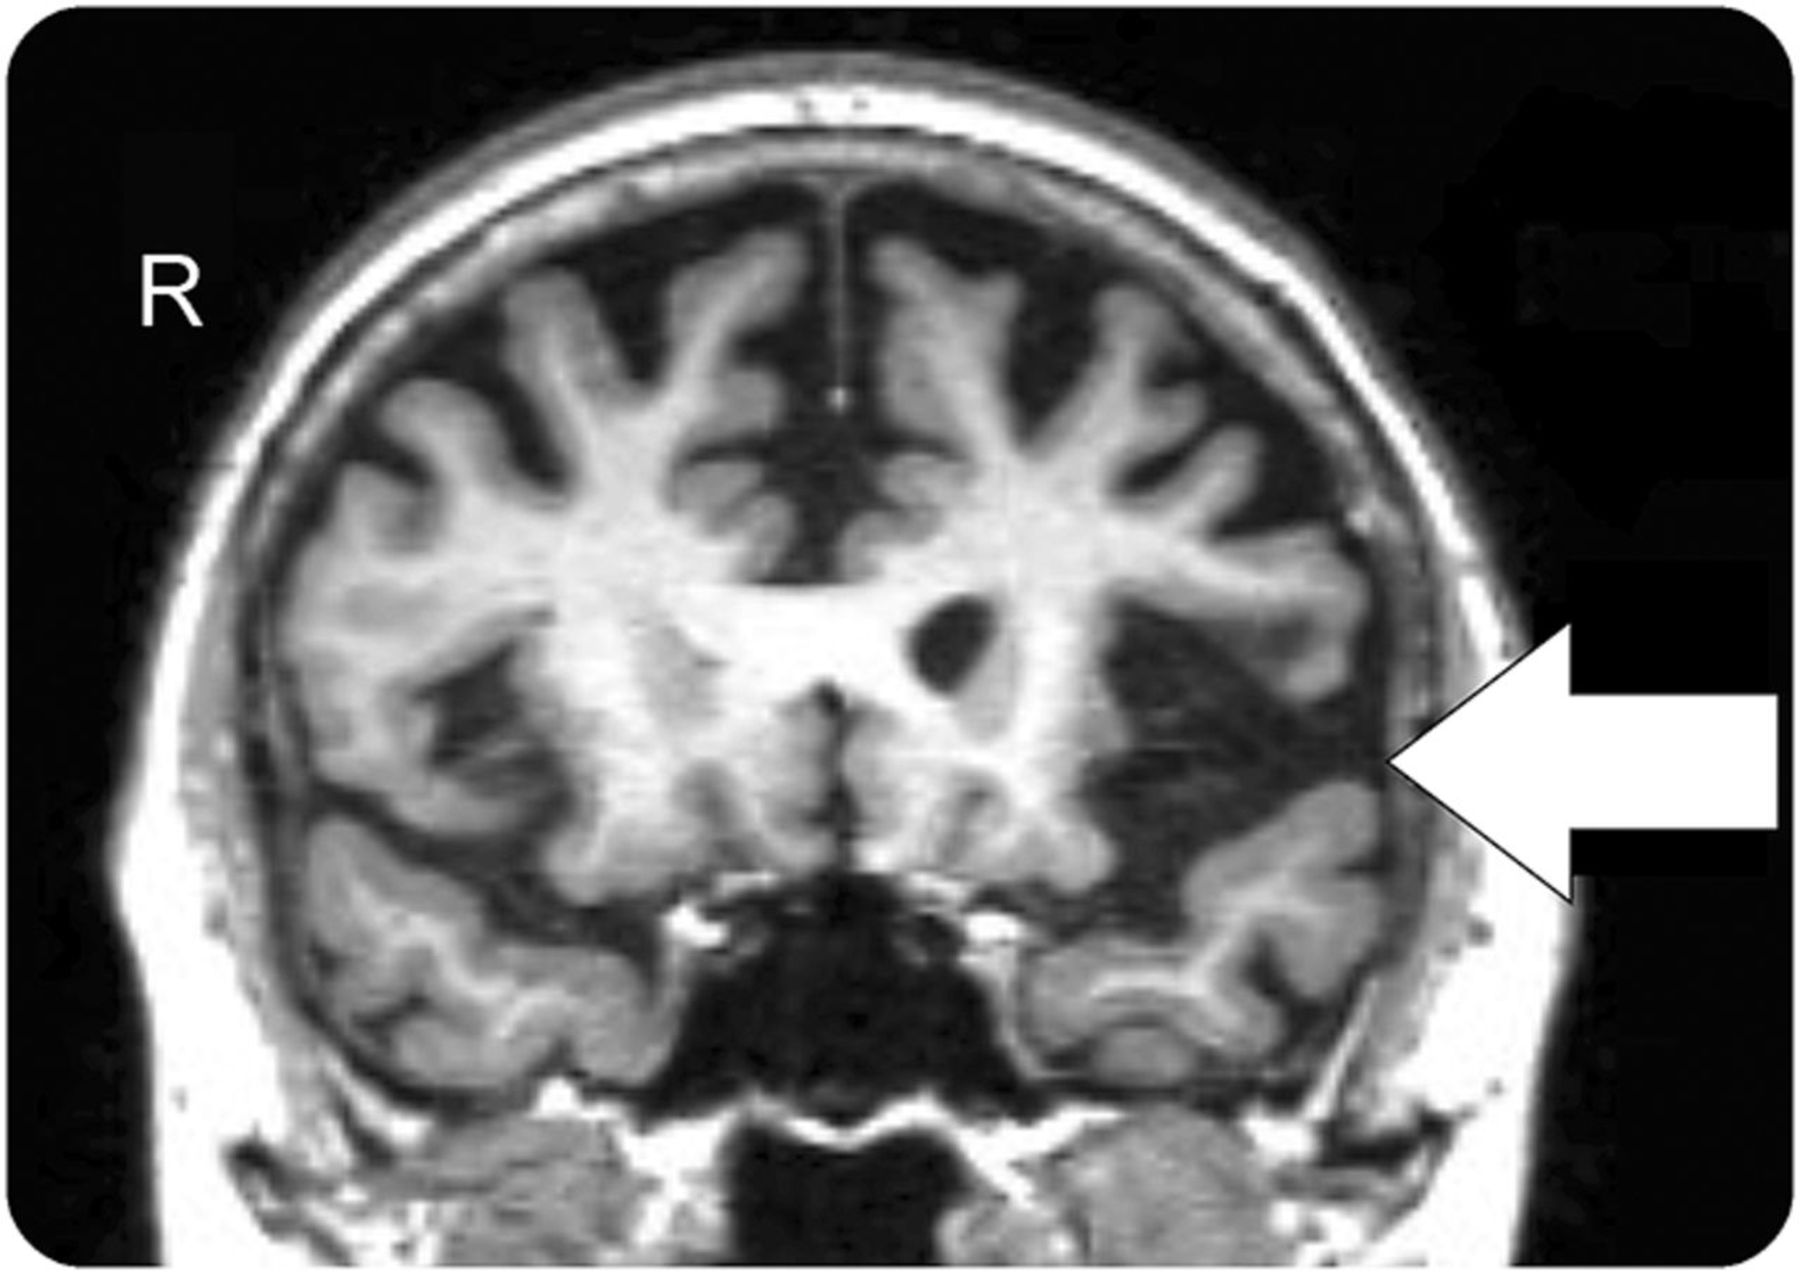

一个66岁的女人面对四年的进步言语困难。她迟滞型语音音素的错误但完整的单字原图理解知识和对象。她的语法是在语音和文字受损,她表现出orofacial失用症。clinico-radiologic(见图)诊断原发性进行性失语迟滞型变体。

迟滞型原发性进行性失语变体在额颞叶痴呆的频谱是一种神经退行性疾病,特点是典型的语言和脑萎缩模式。1最常由于τ病理学,临床医生应该警惕潜在的发展进步的核上的麻痹或corticobasal综合症。2